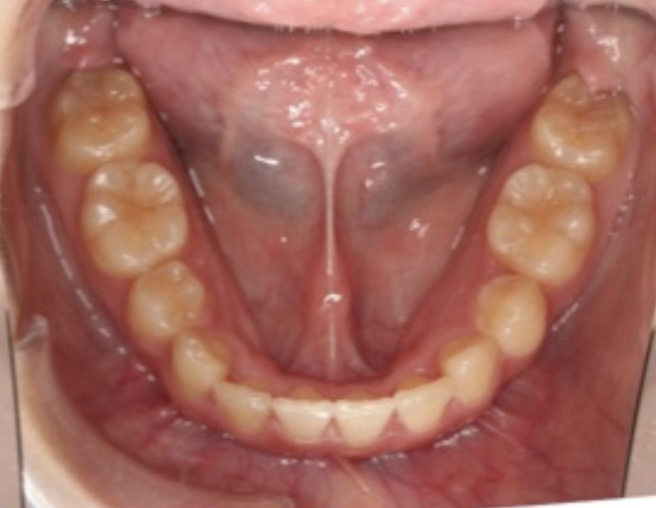

矯正後↓